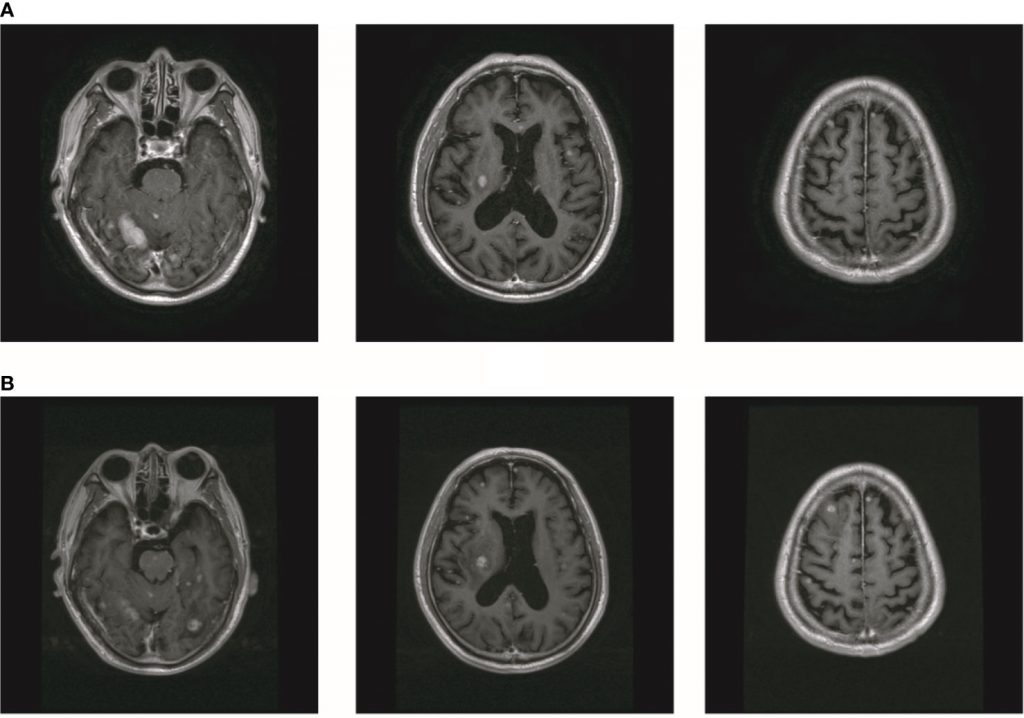

2019年10月,患者出现头晕、右髋疼痛。PET显示右侧髂骨和右侧坐骨多发骨转移(图2A)。此外,大脑中有多个转移灶(图2A)。对比增强磁共振成像(MRI)揭示了九个BM(图2B)。实验室分析显示CEA水平为3.6。我们建议对右侧髂骨进行活检。由于患者颅内压高,头晕加重,他和家人拒绝活检。在通过NGS检查的血液样本中未检测到ALKr 。继刘的报告,患者接受了针对转移灶的全脑放疗(WBRT)联合同步综合强化(SIB)。WBRT的剂量为39.6Gy,分22次给药,SIB的剂量为55Gy,分22次给药(图2C)。患者还接受了右侧髂骨病变的放射治疗(60Gy,24个疗程,图2D)。尽管放疗使患者的右侧髋部疼痛有所改善,但他的颅内压却恶化了。该患者在完成10次颅内放疗后接受了MRI。MRI显示BM的数量增加到大约50(图3A)。经过慎重考虑,我们决定完成WBRT。完成WBRT后,患者昏迷,MRI显示大约80个BM,包括脑干中的一些(图3B)。据报道,根据组织学和配对液基细胞学标本之间的免疫染色,ALK状态的总体一致率为100%。然而,孤立性中枢神经系统(CNS)进展患者的基因组改变检出率较低。由于血液检测结果值得怀疑,患者每天两次接受艾乐替尼Alecensa(Alectinib)600mg。口服艾乐替尼Alecensa(Alectinib)一周后,患者意识逐渐恢复,一个月后身体症状也逐渐好转。MRI显示BM数量减少至约60个,转移肿瘤总体积减少(图4A))。一些转移灶消失了,尤其是在脑干中。然而,由于患者自主终止降压治疗,右侧丘脑出血并破裂入脑室,导致脑出血。患者因脑出血接受治疗。同时,患者继续服用艾乐替尼Alecensa(Alectinib)。出现出血后经过一个月的治疗,患者的病情逐渐稳定。MRI显示大部分血肿被吸收,BMs数量进一步减少至约20个(图4B)。总转移性肿瘤体积也进一步减少。

图3

图3放疗后BM数增加。(A) MR显示脑转移的数量增加到约50。(B) MR显示BM的数量增加到约80。